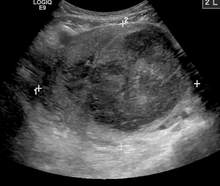

While palpation used in a pelvic examination can typically identify the presence of larger fibroids, gynecologic ultrasonography (ultrasound) has evolved as the standard tool to evaluate the uterus for fibroids. Sonography will depict the fibroids as focal masses with a heterogeneous texture, which usually cause shadowing of the ultrasound beam. The location can be determined and dimensions of the lesion measured. Also magnetic resonance imaging (MRI) can be used to define the depiction of the size and location of the fibroids within the uterus.

A relatively large submucosal leiomyoma; it fills out the major part of the endometrial cavity